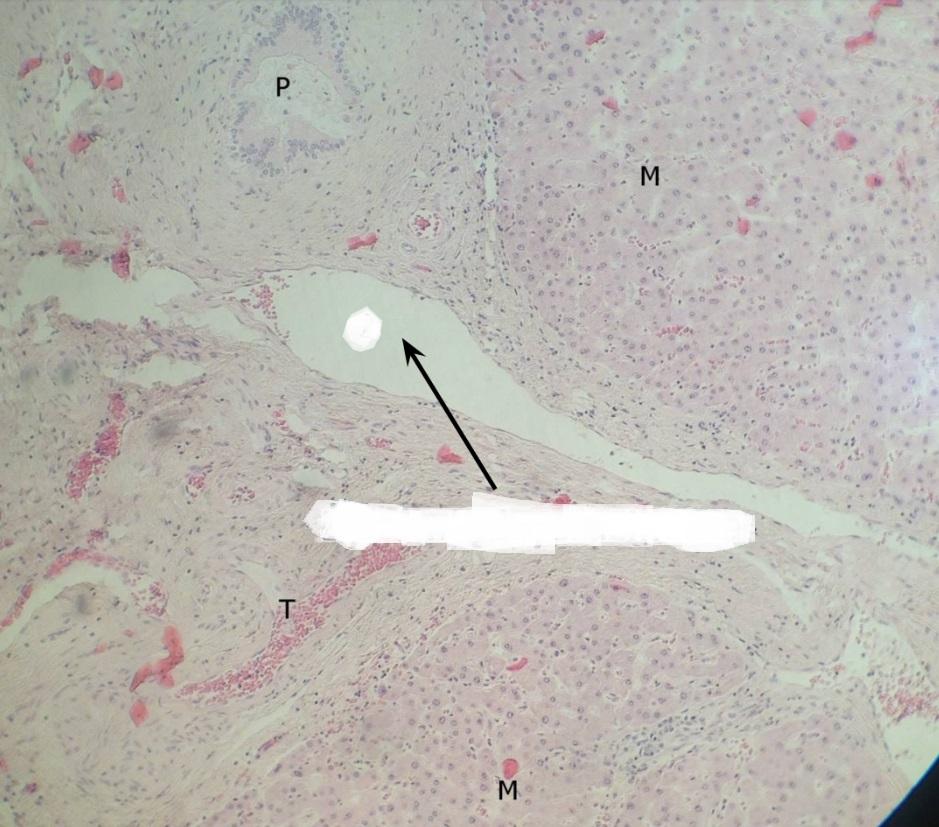

Pytanie 448

hepatocyty (wątroba świni)

Pytanie 449

tkanka łączna (wątroba świni)

Pytanie 450

żyła (jajnik, rdzeń)